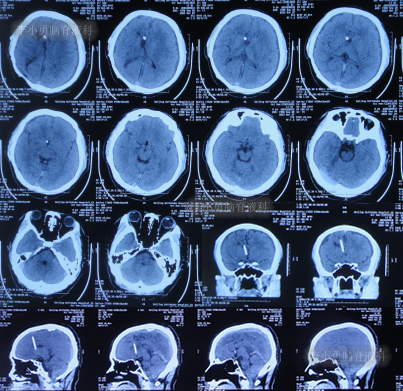

2020年9月2日(李小勇脑脊液科治疗105天)出院,出院时:自己走路速度稍慢,单腿站立不太稳(图-21);出院时头颅CT示未见异常(图-22)。

图-22:出院时头颅CT